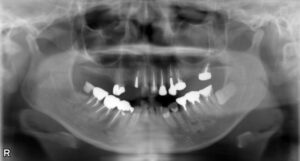

大臼歯2本欠損症例

BEFORE AFTER 43歳女性/上下2本欠損/インプラント埋込手術 【治療内容】 右上第二大臼歯の被せ物が外れてし…